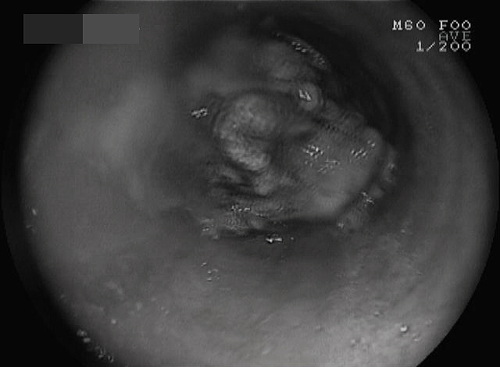

Ngày 12/8, Thạc sĩ - bác sĩ Trần Ngọc Lưu Phương, Phó khoa Nội tiêu hóa, Bệnh viện Nguyễn Tri Phương (TP HCM) cho biết, bệnh nhân 48 tuổi nhập viên vì không ăn uống được kèm tức ngực, nôn ói, nói chuyện khó. "Căn cứ vào lời khai của người bệnh, nghi ngờ nghẹn thức ăn, chúng tôi tiến hành nội soi bằng đường miệng thì không ngoài dự đoán một khối thịt to như quả bóng bàn đang kẹt lại ngay đoạn giữa thực quản", ông Phương nói.

Khối thịt bò chắn giữa thực quản của bệnh nhân. Ảnh chụp màn hình nội soi

Dị vật quá to làm thực quản dãn đe dọa nguy cơ vỡ thực quản nên các bác sĩ phải đưa dụng cụ qua máy nội soi để cắt nhỏ miếng thịt ra, rồi mới gắp ra ngoài an toàn. Nhanh chóng bình phục sau cấp cứu, anh Thanh kể 5 ngày trước anh nhậu và có nuốt thịt bò nhưng nhai không kỹ. "Ngay lập tức tôi biết mình bị nghẹn nhưng nghĩ không sao, nào ngờ tình hình ngày càng nặng", anh này cho biết.